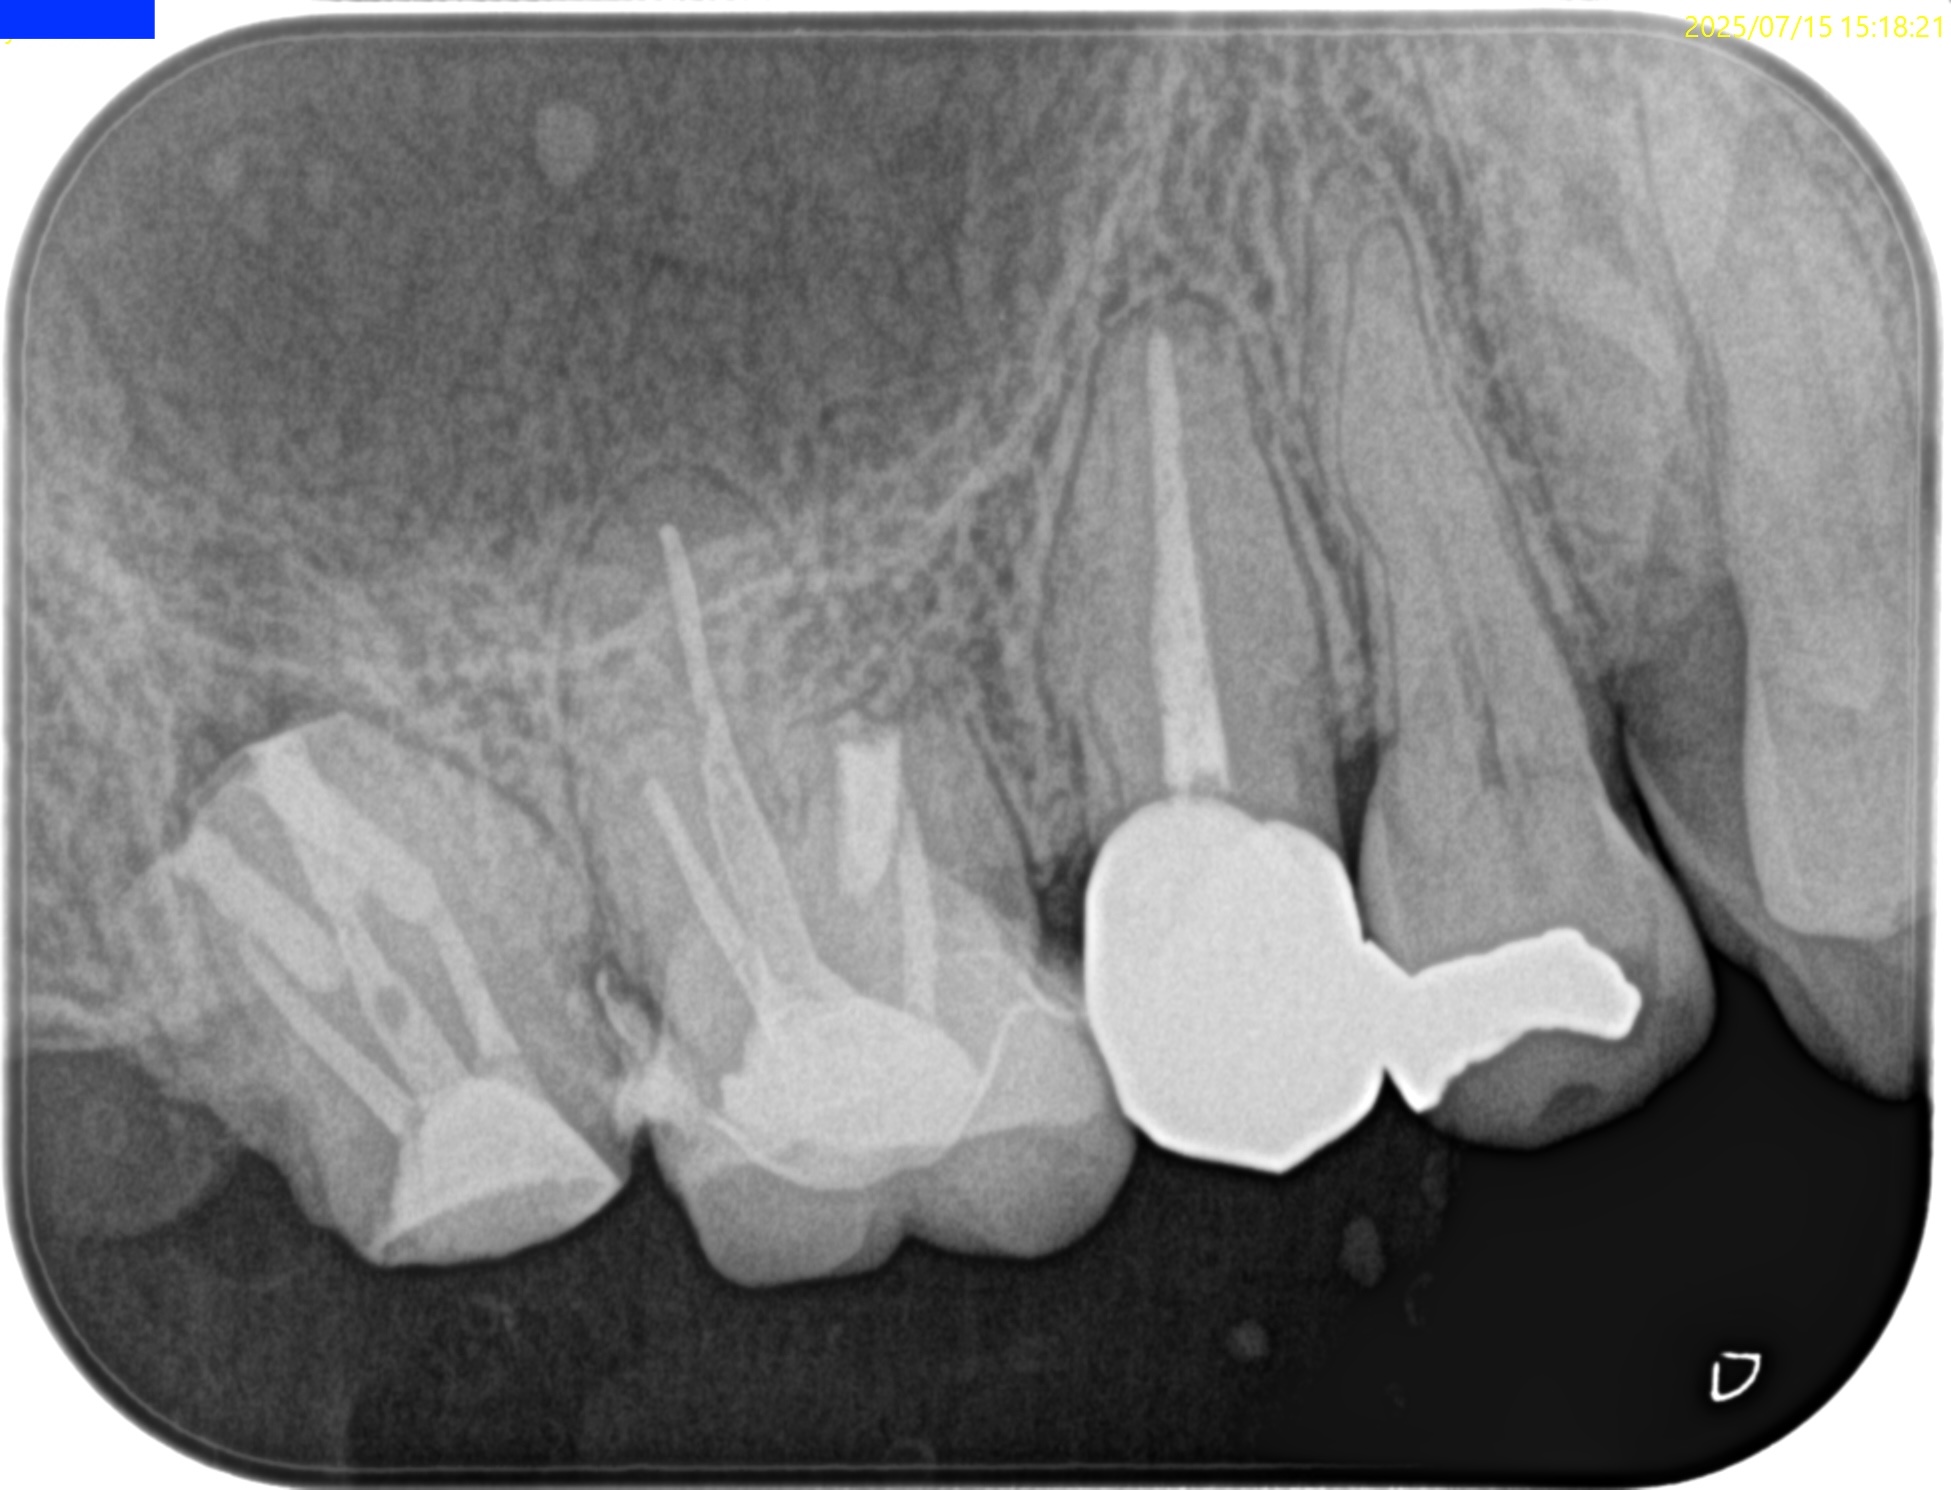

術後にPAを撮影した。

問題はないだろう。

術後に口腔内PA, CBCTも撮影した。

ということで問題が客観的にないことがわかる。